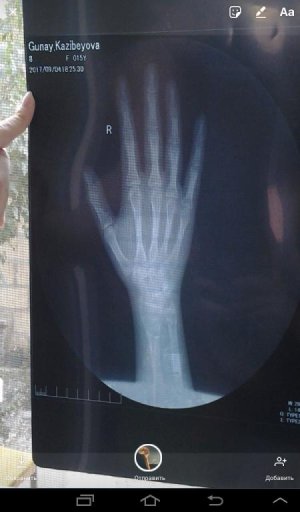

Здравствуйте, я очень передиваю по воводу своего роста, я давно не расту, вчера была у врача, мне сказали, что зоны роста закрыты. Мне в это не верится, мне всего лишь 15 лет. Рост родителей: мама-155, папа-163, мой рост 142. По подсчетам мой рост должен был достигать 159.5. Помогите мне пожалуйста, подскажите, как мне вырасти? Я не могу смириться с тем, что я и в 18, 20, 25, 30, 40 буду роста 142 сантиметра, даж не полтора метра. Я буду очень ждать, помогите мне пожалуйста.